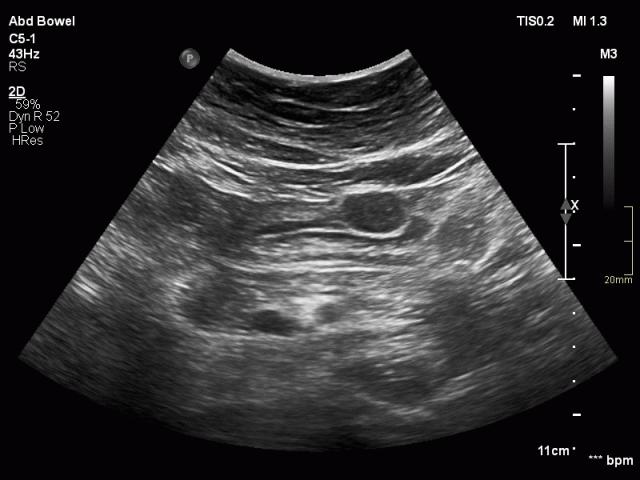

Ruột non được gắn vào mạc treo ruột, được gấp lại như hình chiếc quạt.

Mạc treo chứa một lượng mỡ thay đổi, và mạc treo có mỡ bị gấp nếp tạo ra hình ảnh nhiều lớp, đặc biệt khi bị nén ép trong quá trình siêu âm.

Mạc treo bình thường (mũi tên) ở những bệnh nhân gầy chỉ có thể nhìn thấy khi có cổ trướng.